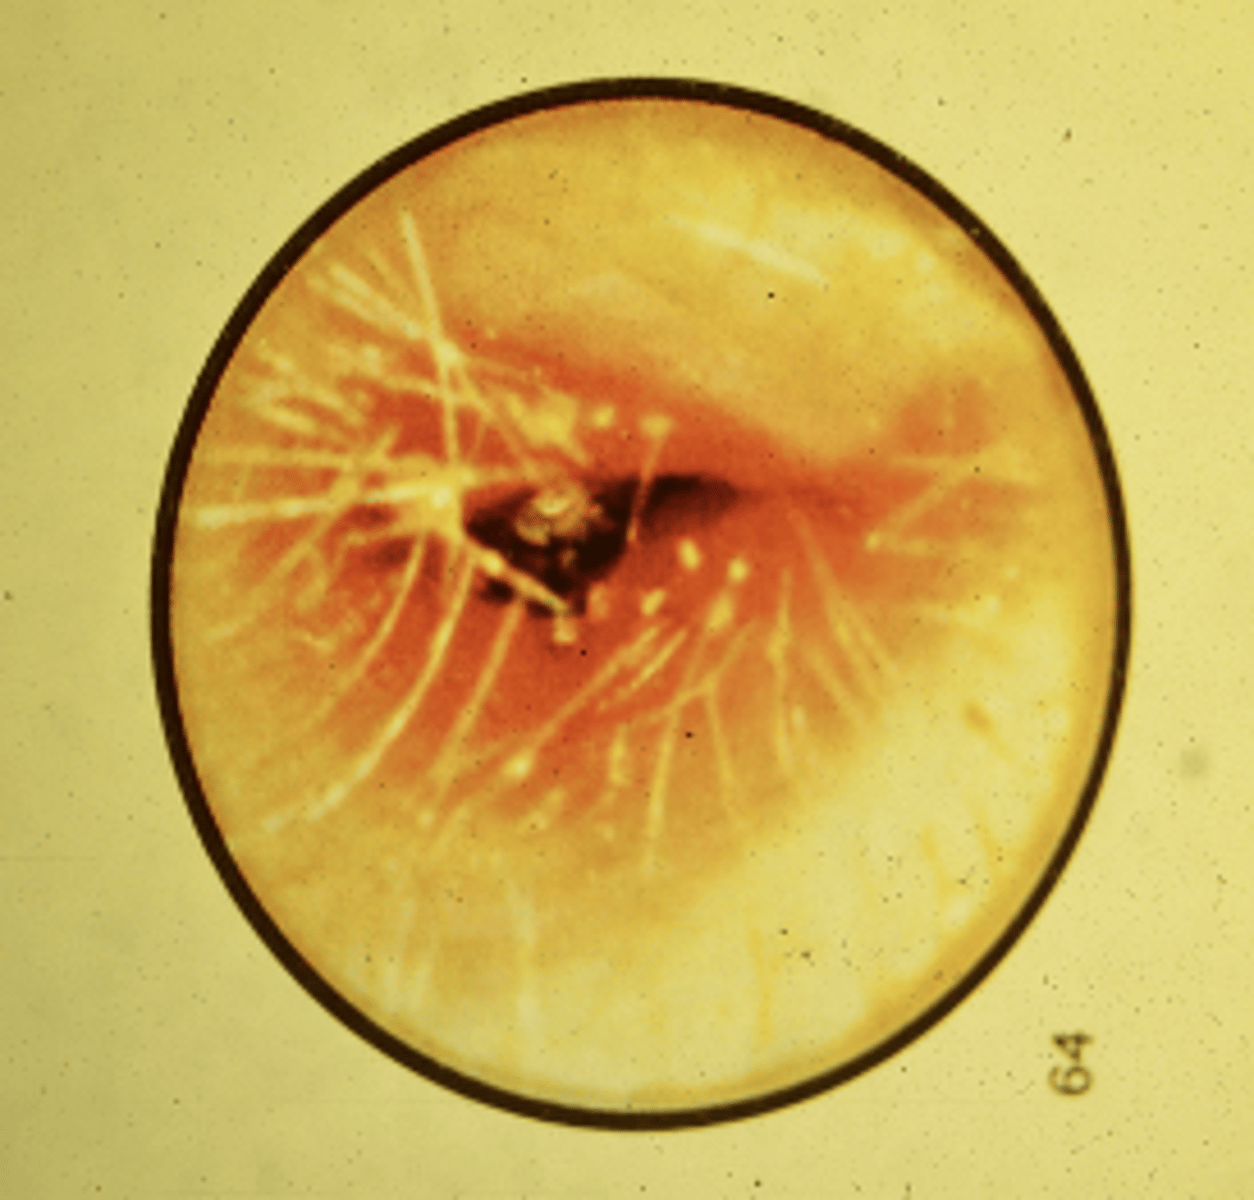

Image shows Acute Otitis Media

-What is this dx of the following image?

Acute Otitis Media

-Agents: Pneumococcus, haemophilus influenza, Streptococcus

-TX: culture if ear drum ruptured; PCN; Macrolides if PCN sensitive; myringotomy